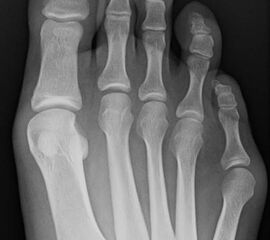

Abb. 7 a, b: Typ II Deformität mit prä- (a) und postoperativem Röntgenbild (b) mit K-Draht Osteosynthese und gleichzeitiger Hallux valgus Korrektur.